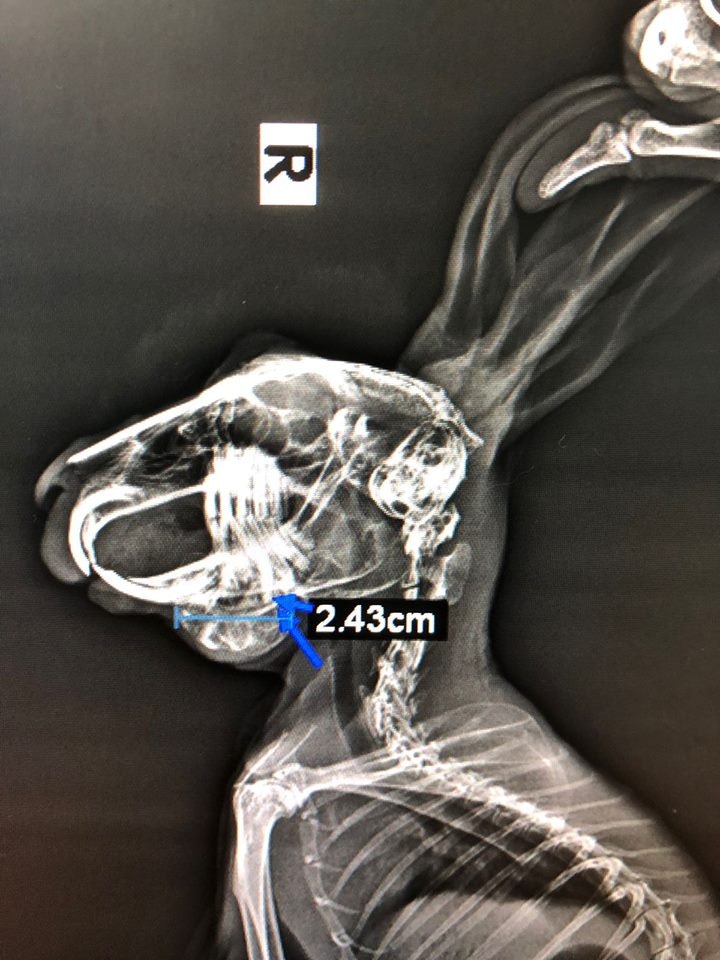

根據醫生的X光片可見,膿瘡大至2.43厘米大。(兔協提供)

6歲半的兔兔Cho Cho,牙齦過長插入顎骨,發炎含膿,長出兩個巨大膿瘡,更曾因痛楚而一度絕食。

6歲半Cho Cho下顎位置長出逾2厘米長的膿瘡,忍受烈痛至一度不願進食。(鄧凱愉攝)